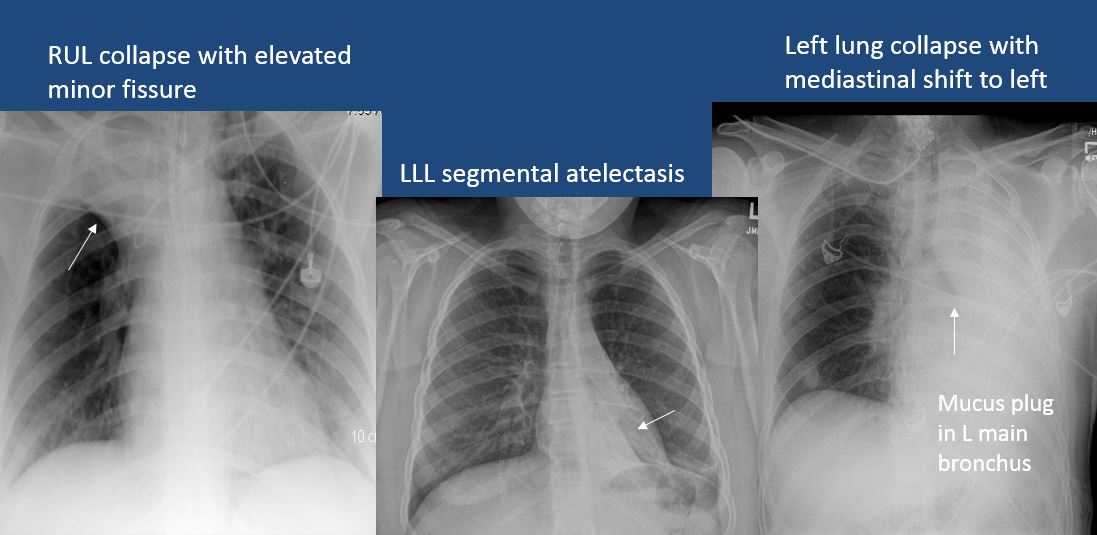

There is focal or lobar atelectasis or total collapse of the lung. [Yes/No]

The position of the major and minor fissures is abnormal. [Yes/No]

There is abnormal shift of the mediastinum. [Yes/No]